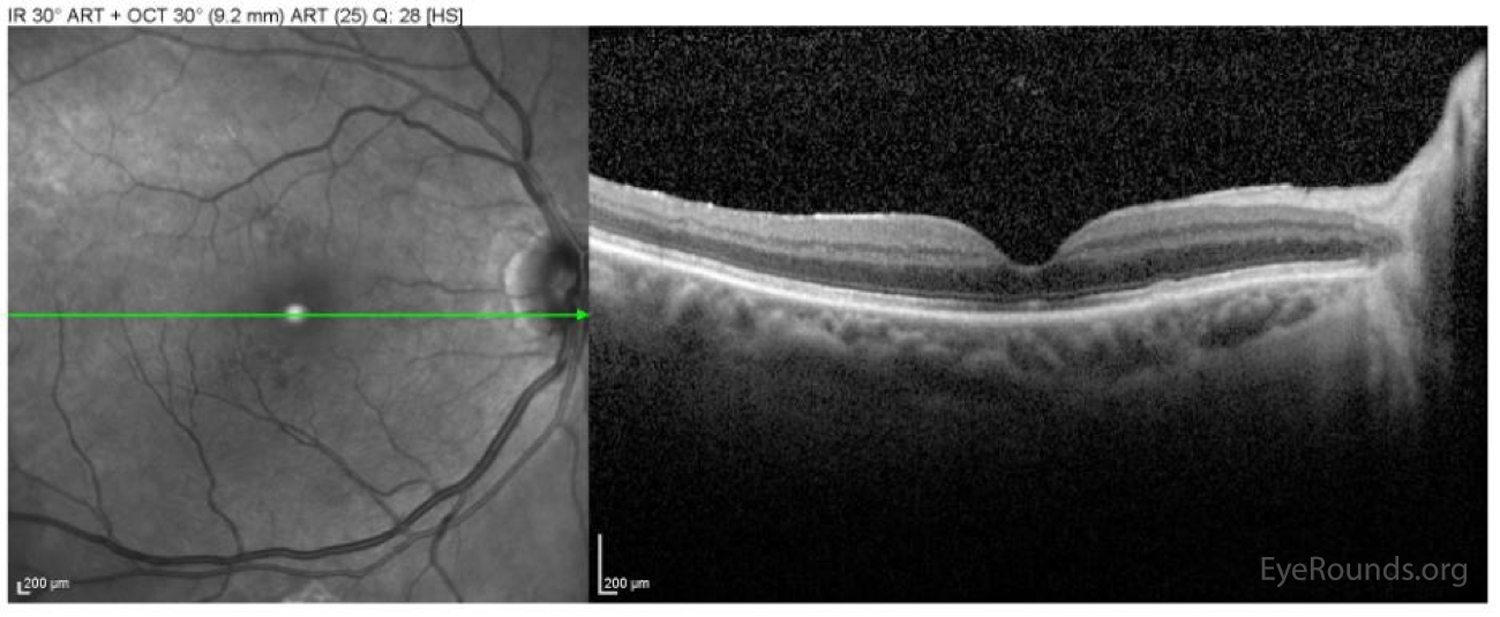

Figure 1: Spectralis ocular coherence tomography (OCT) of the macula OD on initial presentation demonstrating the presence of a full-thickness macular hole with interstitial and subretinal fluid.

Figure 2: Spectralis OCT of the macula OD at the one-month post-operative visit demonstrating interval closure of the macular hole.